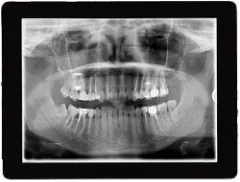

Digital radiography is a type of X-ray imaging where digital X-ray sensors are used instead of traditional photographic film. This technology offers several benefits over conventional methods, making it an invaluable tool in modern dentistry.

One of the primary advantages of digital radiography is the reduced radiation exposure for patients. Digital X-rays use up to 90% less radiation compared to traditional X-rays, making them a safer choice for comprehensive dental imaging.

The images produced by digital radiography are instantly viewable on a computer screen, allowing for immediate analysis and diagnosis. These images can be enhanced and enlarged, providing our team with a high-resolution view of your teeth and surrounding structures. This level of detail aids in accurate diagnosis and effective treatment planning.

Another benefit of digital radiography is its efficiency. The process is quick and comfortable, eliminating the need for film development. This means shorter appointments and more convenience for you.

Digital X-rays are also more environmentally friendly than their traditional counterparts. They eliminate the need for film and film processing chemicals, contributing to a greener planet.